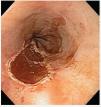

Figura 2. Imagen endoscópica posterior a mucosectomía esofágica en la zona correspondiente a displasia de alto grado en esófago de Barrett.